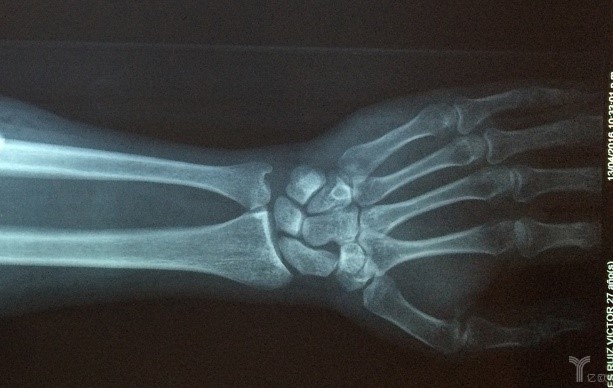

- 腕部骨折檢測軟體OsteoDetect

2018年5月,美國食品藥品管理局(FDA)近日批准了一種名為OsteoDetect的新型人工智慧工具,可幫助醫生診斷手骨骨折。該工具是一種電腦輔助檢測和診斷軟體應用程式,它使用AI演算法來説明醫生以比傳統診斷技術更快的速度確定腕骨骨折。

FDA表示,該軟體可識別骨折(如果存在)並自動將其標記在圖像上,説明醫生快速發現並診斷問題。該軟體適用于成人手腕並可識別橈骨遠端骨折。急診室,初級保健辦公室和緊急護理設施等均可以從這種技術中受益。重要的是要注意,該軟體不會取代醫療保健專家; 相反,它被分類為附屬工具。

OsteoDetect研發公司展示了這個AI軟體通過涉及1000張X射線圖像的研究診斷腕骨骨折的有用性,以及另一項涉及24位提供者的研究,這些研究人員共檢查了200例病例。FDA稱,這兩項研究表明OsteoDetect改善了腕骨骨折的檢測和診斷。